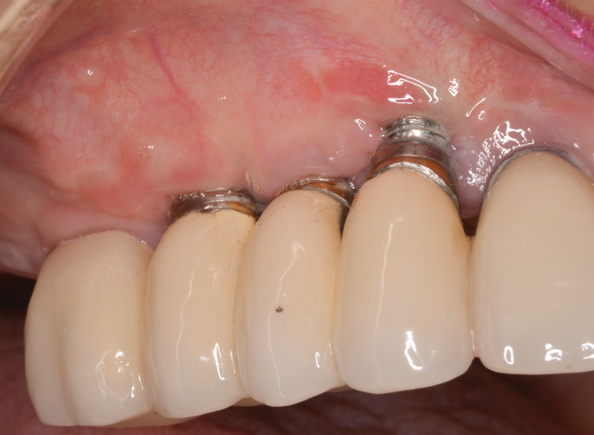

(13.) Reverse torqueing allows for a nonsurgical implant removal. No bone was sacrificed in removing these three implants.

Figure 13

(14.) One-time use reverse torque components were used to remove these implants. Portions of osseointegrated bone are still attached in the apical region.

Figure 14